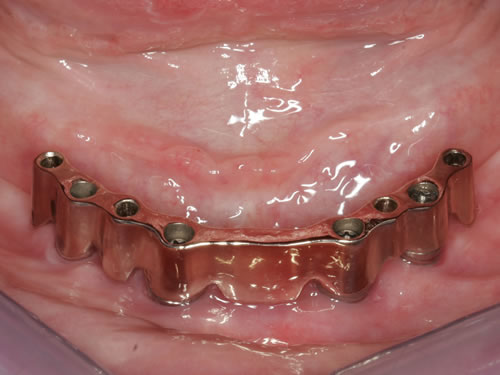

Für den zahnlosen Ober- und Unterkiefer werden dies häufiger Stegkonstruktionen oder Teleskopversorgungen sein (Abb. 8.8 bis 8.16).

Abb. 8.8: Individueller Steg auf 4 Implantaten im zahnlosen Unterkiefer.

Abb. 8.10: Individueller Stahlsteg auf 4 Implantaten im zahnlosen Oberkiefer.

Abb. 8.12: Zahnloser Oberkiefer mit 8 Implantaten und eingesetzter Unterkonstruktionen.